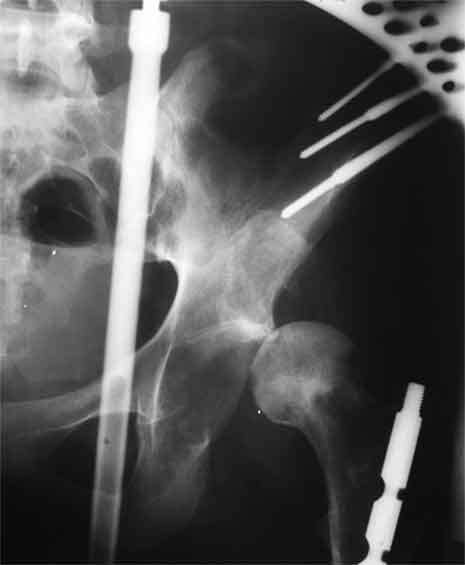

у нас, вероятно, первым этапом наложили бы аппарат таз-бедро без резекции головки, потом протезирование после восстановления длины.

> у нас, вероятно, первым этапом наложили бы аппарат таз-бедро без

> резекции головки, потом протезирование после восстановления длины.

Получится ли низвести головку? Там, скорее всего очень плотное фиброзное сращение. У нас такого опыта закрытого низведения не было. По вашему мнению, сколько времени может уйти на низведение до 8 см? И какая компоновка АВФ?

Насчет 8 см согласен с А.Н. Челноковым, это наверное ортопедическое за счет приводящей, сгибательной контрактуры и, возможно, колена. на ликвидацию укорочения у нас обычно уходит около 2-х нед. снимки в приложении, возможно не очень показательные, но других с ходу не нашел, завтра еще поищу.

Метод беcкровного низведения, предложенный Max&Co, мне кажется более логичным, чем поэтапность с удалением головки и с дальнейшим скелетним вытяжением.

Протезировать можно одномоментно, но тогда потеряется эффект от дистракции на мобильном аппарате. На дистрагированных мягких тканях по

Илизарову "закон напряжения растяжения" (tension stress) лучше делать реконструктивные операции, чем на контрагированных, твердых, как камень мышцах.

Другое преимущество - больной, самостоятельно передвигаясь, не будет обузой для обслуживающего персонала и в течение первого этапа может

находиться дома. После достижения дистракции отпадет необходимость предлагаемого двойного доступа с кровотечением!!, которые послеоперационно имеют большую вероятность осложнений, например, вывих протеза из-за ослабления сустава со всех сторон.